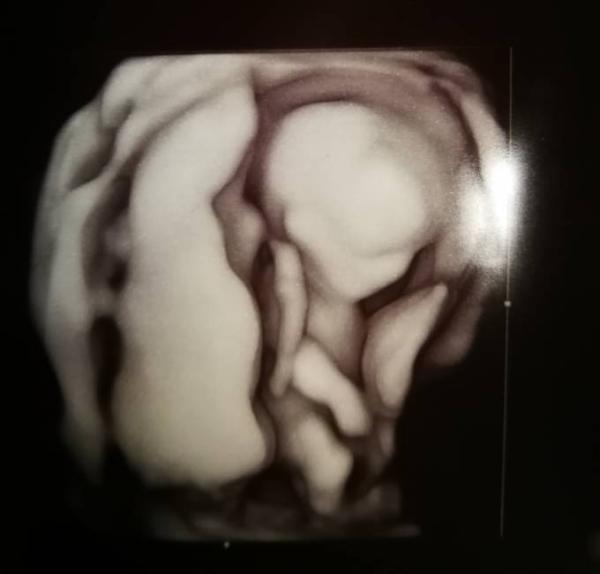

Guten Morgen zusammen, wir hatten gestern unser lang ersehntes ETS und es war atemberaubend... einfach unbeschreiblich wie schön...wir hatten die beiden Jungs dabei(5+8) und Vorallem für den großen sehr sehr interessant, leider lag der kleine Knirps nicht so geschickt und hatte nochdazu die Beine überkreuzt...er hat es dann noch mit einem anderen Gerät versucht und dann sah man auch zwischen die Beinchen, für mich sah es eindeutig nach Junge aus, der Arzt meinte man könne es jetzt noch nicht sagen...aber es war alles bestens und ich kann es nur jedem empfehlen, man sieht wirklich alles, jeden einzelnen Zeh, jeden Finger, die Nieren, Magen, einfach alles...ich habe gleich eine Risikobestimmung für eine Präeklampsie machen lassen, da ich davon jetzt hier schon öfter gelesen habe und wenn man dem vorbeugen kann, möchte ich es natürlich wissen...ich wünsche euch einen guten Start in den Tag Achja es ist jetzt in der 12+4 7;5 cm groß, unglaublich wie schnell die Würmer wachsen

Bild zu ETS - Forum für April - Mamis